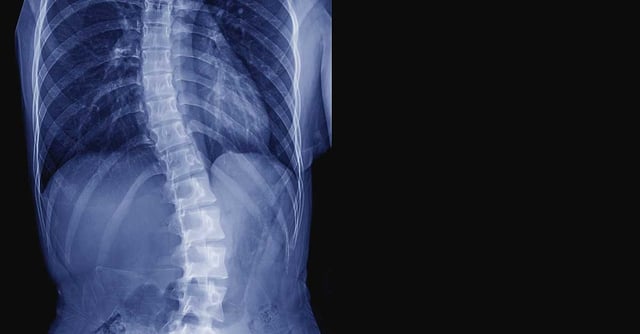

Scoliosis means that the spine curves sideways instead of being straight. Children with cerebral palsy have significant risk of developing scoliosis and it is thought to be associated with:

These factors can cause the spine to bend or twist, especially as your child grows. The curve may start small but can gradually increase.

Research shows that hip problems are a major contributor to pelvic tilt. When the pelvis tilts, the spine must curve to keep the body upright. This can lead to scoliosis — often bending away from the high side of the pelvis as the spine tries to find balance.

The influence also goes the other way. If scoliosis develops first, especially a curve involving the lower spine:

- It can pull the pelvis out of alignment.

- The child may sit more heavily on one side, increasing pressure on one hip.

- Over time, this uneven loading can worsen hip displacement.